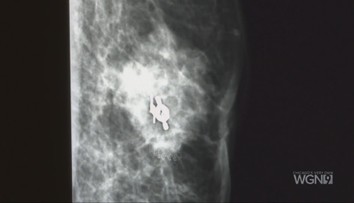

Hrčka na prsníku Žilinčanke narástla do obrovských rozmerov

Zanedbať hrčku v prsníku sa nevypláca. Presvedčila sa o tom aj 37-ročná Žilinčanka.

Nezhubný nádor jej za pár rokov bez návštevy lekára narástol do bizarných rozmerov. Plastický chirurg doposiaľ nič podobné nevidel.